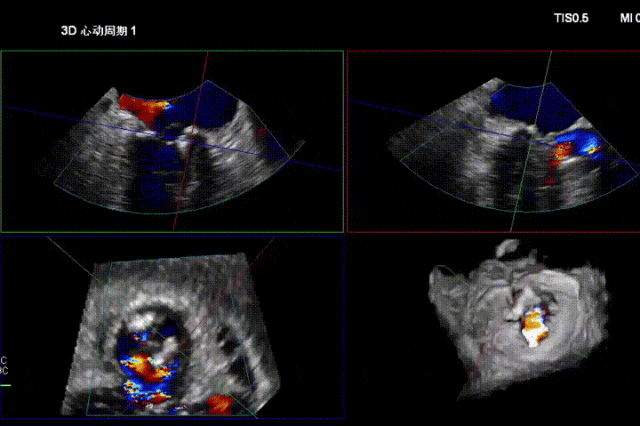

术前经食道超声显示:二尖瓣C1、P1区脱垂,重度关闭不全,彩色多普勒提示大量二尖瓣反流。术前瓣口面积MVA约5cm²,瓣环前后径AP约36.9mm,前叶A1约26mm,后叶P1约15.2mm。

患者全麻后仰卧位,常规消毒铺巾,置入下食道超声探头。于左前胸第五肋间做小切口,暴露心尖,全身肝素化后,心尖穿刺,逐步送入二尖瓣夹系统。术中在超声引导下,分别于C1及A1/P1区植入2枚ValveClamp®二型(MVC-Ⅱf)二尖瓣夹,夹合后超声显示二尖瓣反流明显减轻,随即释放夹子。术后置左侧胸腔引流管1根,逐层关闭胸壁,患者顺利转入ICU观察。

术后即刻反流降为少量,剩余瓣口面积2.57cm²,平均跨瓣压差2mmHg。